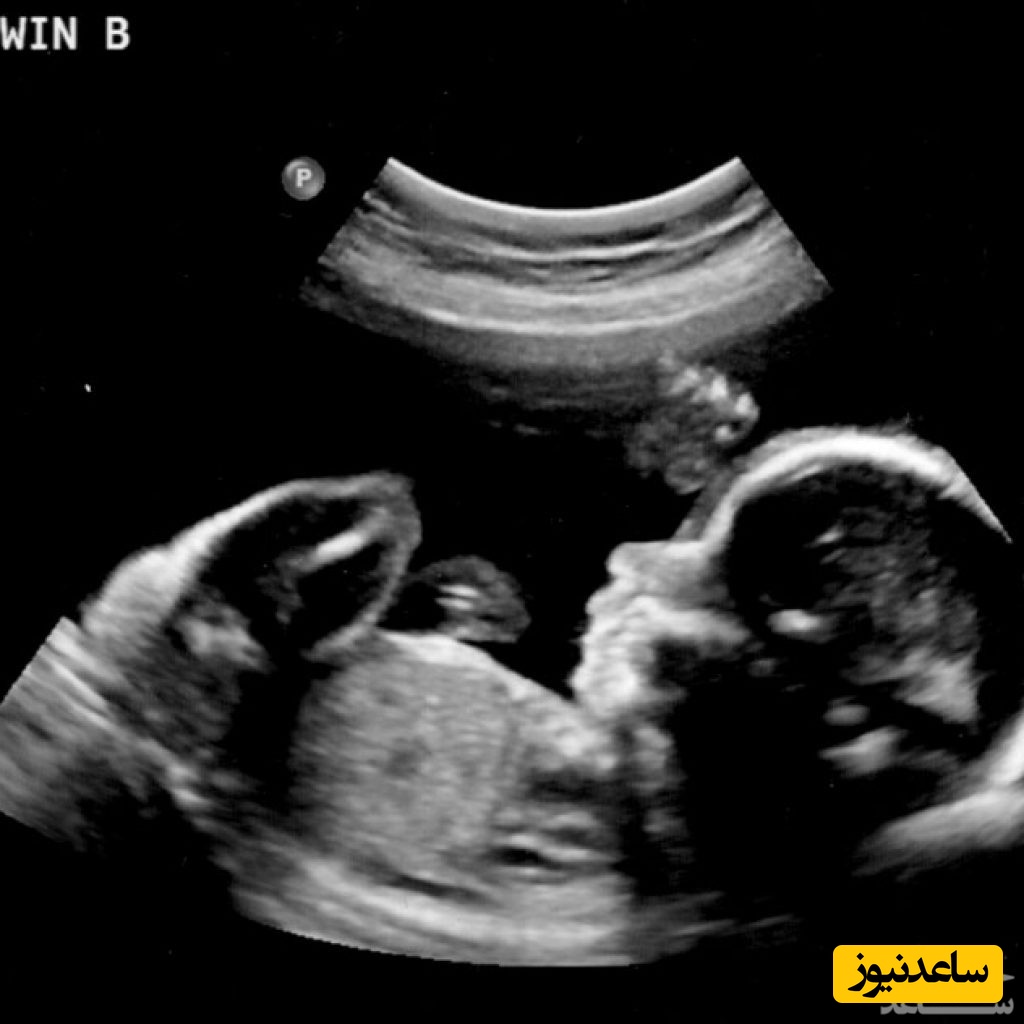

در یک دختر، برامدگی تناسلی به کلوتری و لابیا تبدیل خواهد شد. این یک فرآیند تدریجی است و در حدود 11 هفتگی رخ می دهد که تفاوت بین دختر و پسر را می سازد.در این مرحله، همه کودکان یک چیزی دارند که از آنها بیرون زده است ؛ در پسرها، به سمت بالا به نظر می رسد که در یک زاویه بیش از 30 درجه از ستون فقرات قرار دارد و در دختران، بیشتر افقی است، با زاویه ای کم تر از 30 درجه.نوزاد باید به پشت دراز کشیده باشد تا این موضوع را ببیند.تصاویری که بلافاصله در زیر آورده شده اند از دو نوزادی هستند که در طول هفته 13 ام بارداری هستند و برامدگی تناسلی را نشان می دهد. نوزاد در سمت چپ یک آلت تناسلی دارد که در زاویه ای است که بیشتر از 30 درجه قرار دارد، پس احتمالاً یک پسر است. همچنین شبیه آلت تناسلی و کیسه بیضه نیز هست.

نوزاد در سمت راست یک آلت تناسلی دارد که بیشتر افقی است، موازی با ستون فقرات، بنابراین او احتمالاً دختر است. تفاوت میان دو بچه بالا کاملاً مشخص است، اما همیشه هم روشن نیست. در حقیقت، مطالعات نشان می دهند که این یک اتفاق زیبا و دلنشین است.تحقیقات اولیه نشان داد در کودکانی که در وضعیت دراز کشیده قرار دارند، با استفاده از ماشین های اسکن بسیار حرفه ای، در هفته 11 ام تنها 70 درصدجنسیت مشخص می شود، و ظرف مدت 12 هفته از هر 10 مورد، 9 مورد گزارش کردند. در مطالعه ای دیگر، سونوگرافی تنها می تواند در حدود 46 درصد از کودکان را در هفته 12 ام و 80 درصد در 13 هفته به درستی تشخیص دهد.